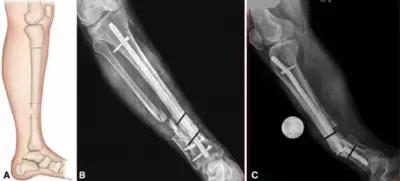

因为骨痂的生长没有感觉,所以患者最好在骨折后1个月,3个月,6个月到医院拍片检查,如果出现骨痂没有生长,骨折线清晰的状况,要连续两个月,每月检查。连续3个月骨痂没有生长,就是有骨不愈合的倾向,要及时治疗。